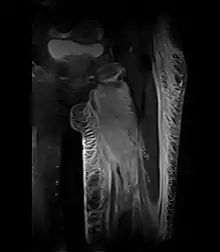

Creatine kinase may be normal or increased probably depending upon the stage of the condition when sampling is undertaken. ESR is elevated. Planar X-ray reveals soft tissue swelling and may potentially show gas within necrotic muscle, Bone scan may show non specific uptake later in the course. CT shows muscle oedema with preserved tissue planes (non-contrast enhancing). MRI is the exam of choice and shows increased signal on T2 weighted images within areas of muscle oedema. Contrast enhancement is helpful but must be weighed against the risk of Nephrogenic Systemic Fibrosis as many diabetics have underlying chronic kidney disease. Arteriography reveals large and medium vessel arteriosclerosis occasionally with dye within the area of tissue infarction. Electromyography shows non specific focal changes.